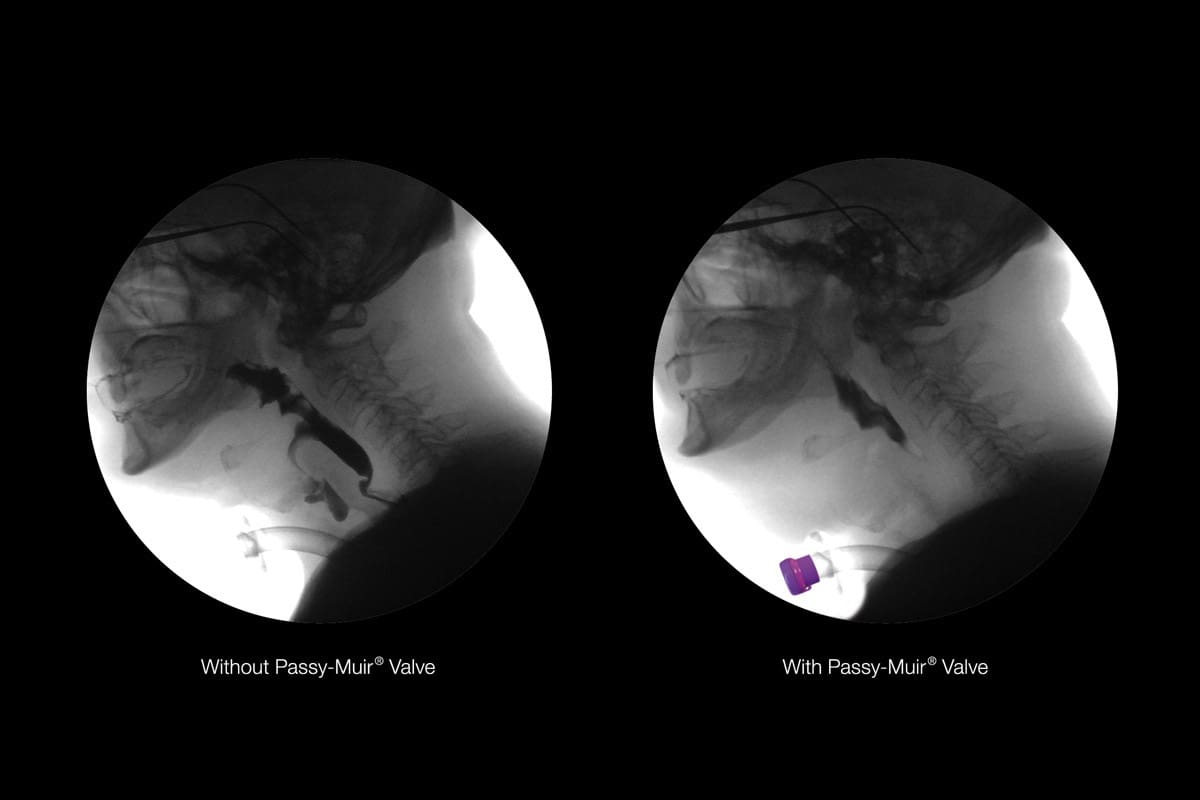

Tracheostomy Pressures